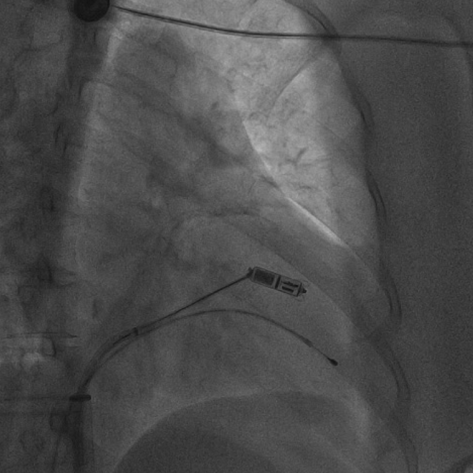

无导线起搏器被抓捕、拔除的术中影像

术前,汤宝鹏教授带领治疗团队对文献进行了详细查阅,对病情进行了充分而细致地评估,对术中可能出现的各种风险做好了各项应急预案。术中,手术团队使用圈套器成功抓捕无导线起搏器Micra尾端并顺利拔除,同时给患者植入左束支心脏再同步起搏除颤器。手术顺利,患者术后恢复良好。